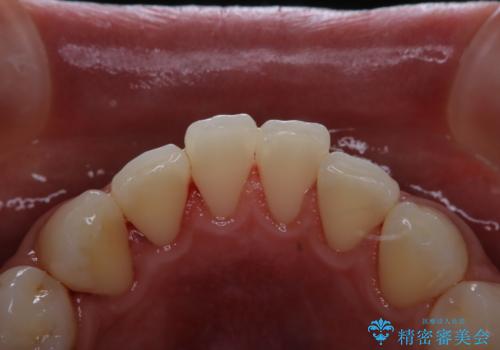

茶渋による着色と下の前歯の裏側のべったり歯石

担当医 歯科衛生士